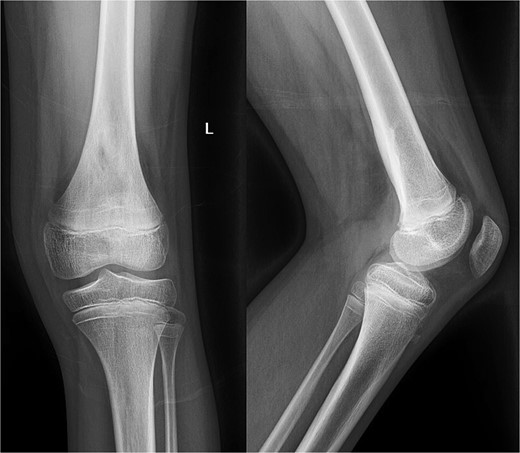

An 11-year-old healthy male presented with posterior left knee pain, which began 4 days after twisting his knee at a trampoline park. The pain progressed to a point where he was unable to bear weight on his left leg, and the knee became locked in flexion due to muscle spasms and pain. After three visits to outside facilities over 2 weeks, the patient finally received an orthopedic consultation. While radiographs were unremarkable, magnetic resonance imaging (MRI) revealed a large fluid collection posterior to the distal femur, suggestive of osteomyelitis, and Brodie’s abscess and associated local destruction of the posterior femoral cortex (Fig. 1a and c). The patient was then transferred to our institution for definitive management. Upon presentation, the patient was febrile (39°C) and nauseous with one episode of emesis. Physical examination revealed a tender and warmer left knee without open wounds. The patient denied a knowledge of current dental carries or a history of recent dental procedures and denied recent history of a streptococcal infection. Laboratory tests showed leukocytosis of 14 600 μl of white blood cells (WBC), elevated C-reactive protein (CRP) of 18 μg/ml (normal <0.3 μg/ml), and an elevated erythrocyte sedimentation rate (ESR) of 18 mm/h (normal <15 mm/h). A CT scan at our institution recapitulated findings suggestive of osteomyelitis, cortical destruction, and a noted thrombophlebitis of the popliteal vein (Fig. 1b).

Preoperative radiography, CT, and MRI. The radiographs were read as normal by the radiology, while the CT and MRI were read osteomyelitis with Brodie’s abscess involving the distal femoral epimetaphysis with destruction of the posterior cortex and associated 7 cm popliteal fossa abscess, along with a suspected nonocclusive septic thrombophlebitis of the popliteal vein mentioned in the report on the CT.

Despite initial improvement, the patient’s CRP stabilized at 5.5 μg/ml 6 days post-operatively. Consequently, a repeat I&D with antibiotic bead placement was performed on postoperative Day 7. The patient’s condition improved, with undetectable CRP levels at discharge 14 days after initial hospitalization. Four weeks post-discharge, a repeat venous ultrasound of the affect extremity was performed, demonstrating resolution of the DVT (Fig. 2). In total, the patient received 18 weeks of outpatient oral antibiotic therapy and 9 weeks of anticoagulation therapy. Six months post-hospitalization, the patient was asymptomatic and cleared to return to full activity. After 1-year post-discharge, final radiographs demonstrated no osseous abnormalities, the patient remained asymptomatic, and was released from clinic (Figs 3 and 4).

Radiography obtained 1-year postoperatively, demonstrating no acute osseous changes.